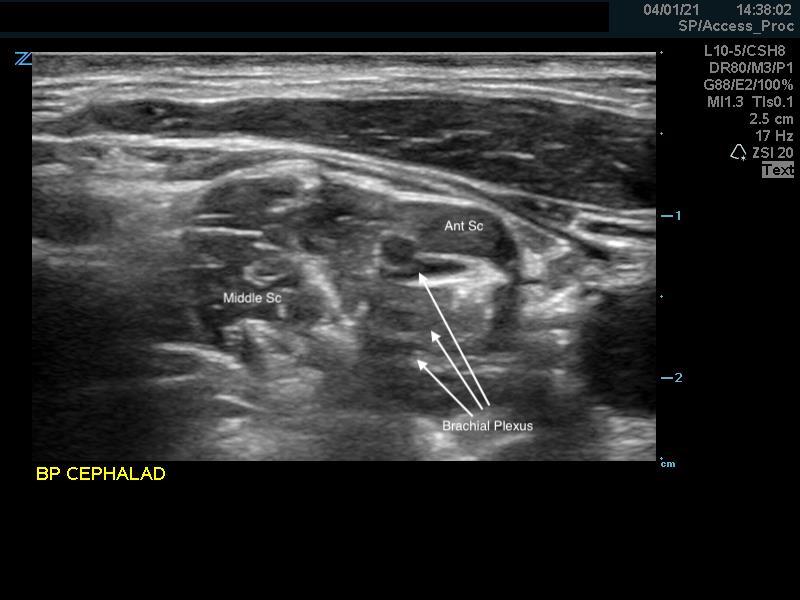

- Identify the middle scalene muscle posterior to the anterior scalene muscle.

- The interscalene space is between these 2 scalene muscles and contains the brachial plexus

- Visualize the brachial plexus here as a stack of circles with hypoechoic centers

- The plexus will look more echogenic, bundled and honeycombed in the caudal interscalene space

- Alternative Pre-scan – Backtracking from the Supraclavicular Space

- Identify the brachial plexus in the supraclavicular fossa as in the supraclavicular brachial plexus block

- The subclavian artery is the main landmark at this site.

- The brachial plexus is seen immediately adjacent to the superior-posterior border of the subclavian artery as a grouping of small hyperechoic circles with hypoechoic centers, similar to a cluster of grapes.

- Backtrack from this site to the interscalene space by sliding the probe cephalad while keeping the plexus in the center of the image.

- The plexus will change conformation and become more hypoechoic as you slide superiorly.